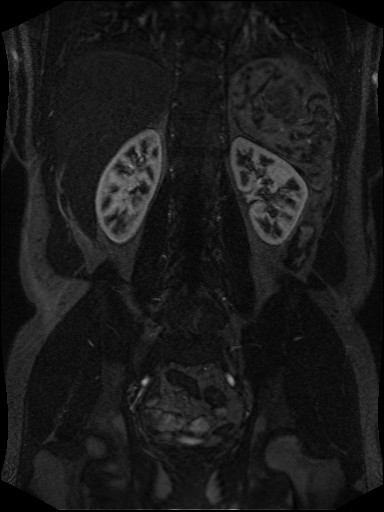

Example of MR Angiography with recording time before and after contrast agent infusion, respectively:

What do we see: Mainly kidneys, liver and and main supporting vessels aggregate contrast agent.